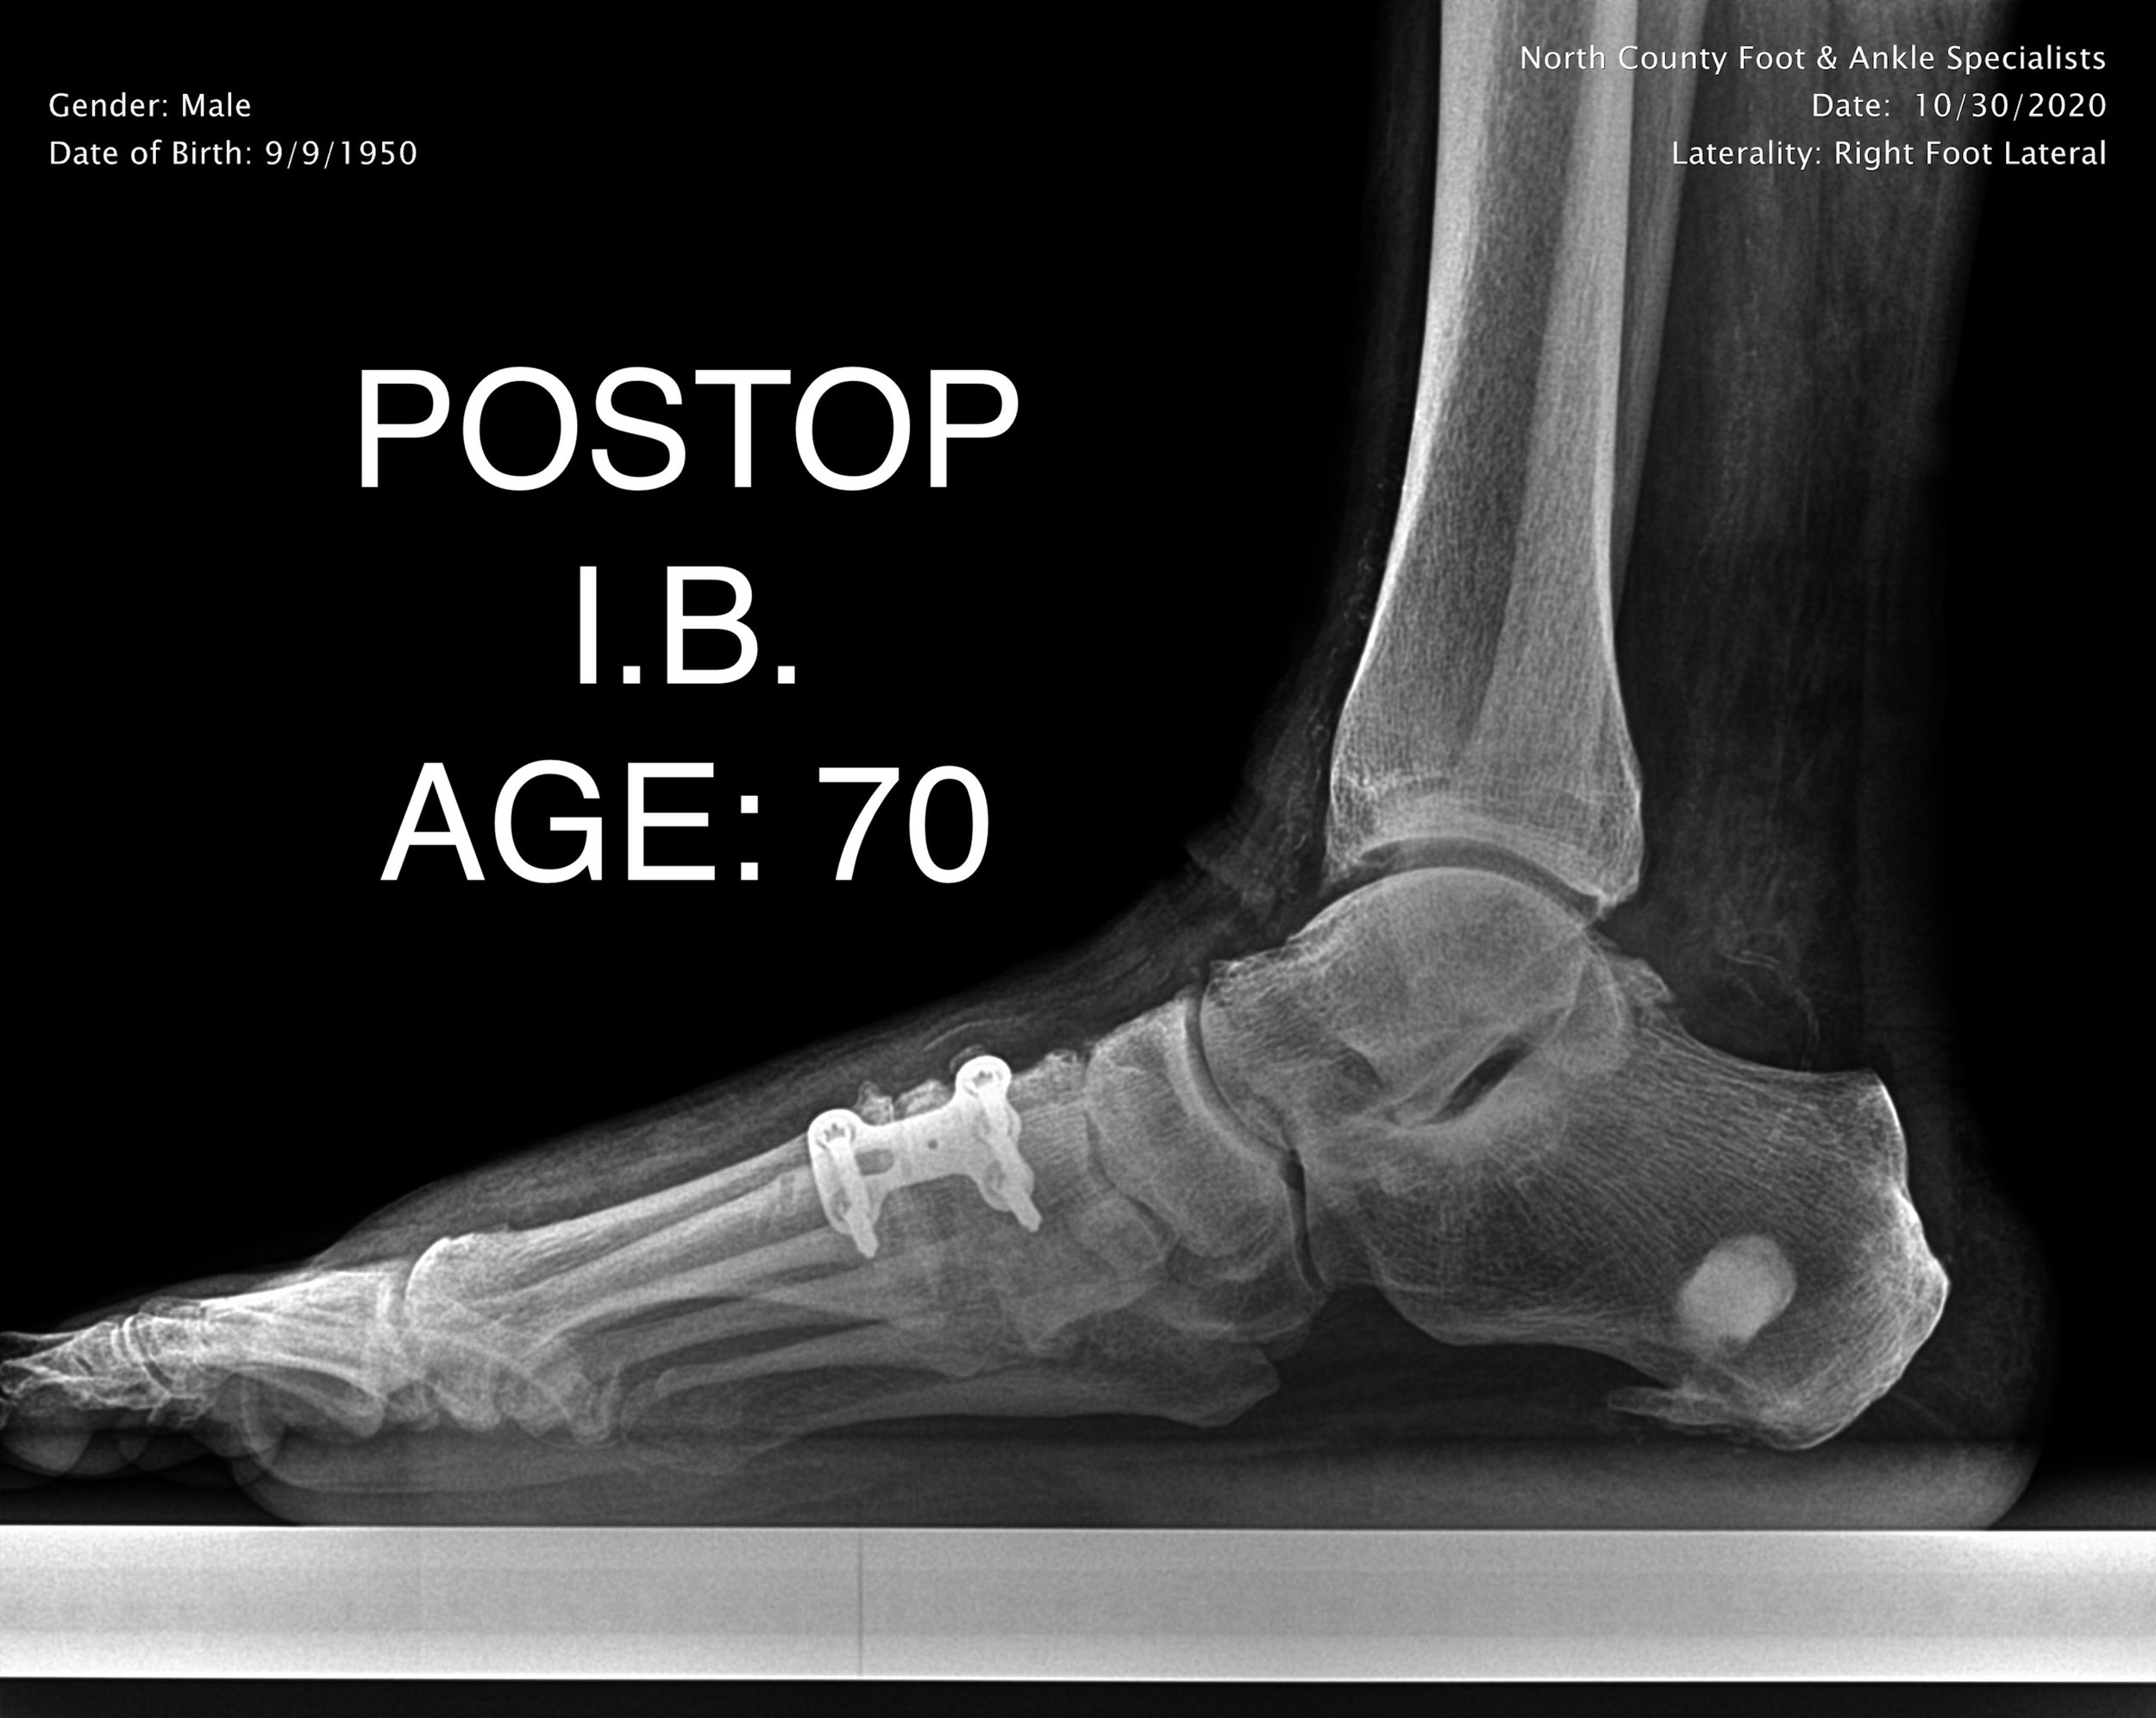

ADULT FLAT FOOT RECON